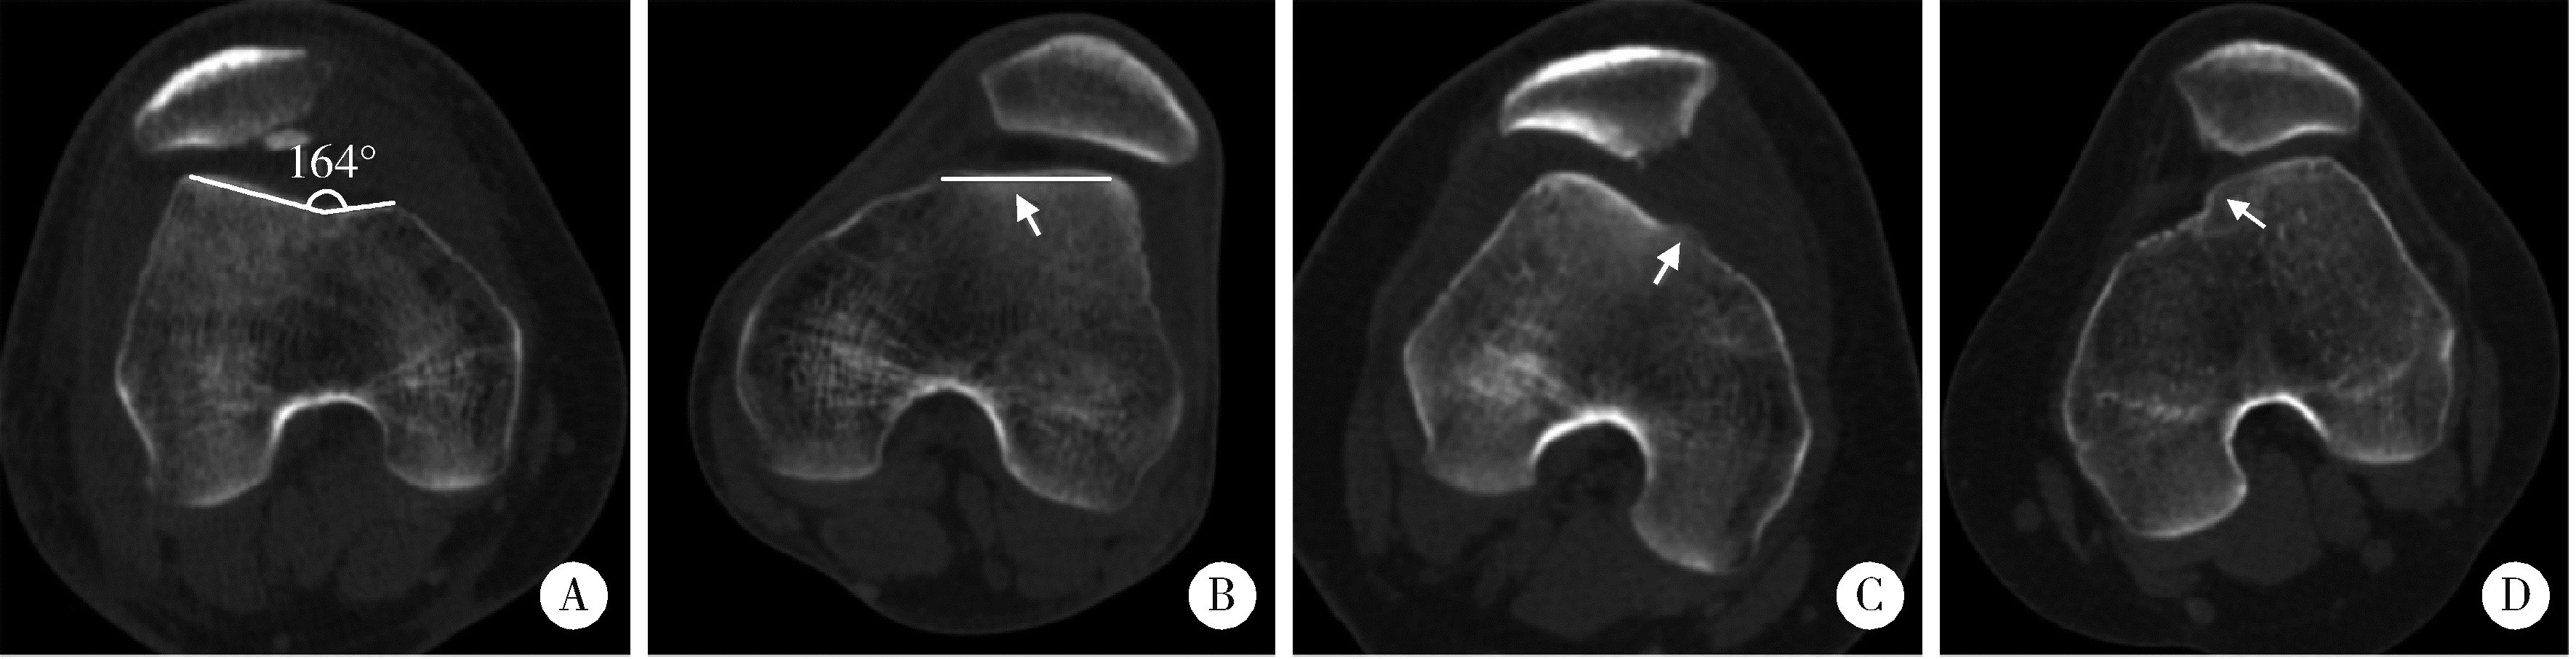

图3 侧位X线及轴位CT影像学指标的测量方法

Figure 3 Measurements of radiographic parameters on lateral plain radiographs and axial CT

A, Insall-Salvati index is the ratio of the patellar tendon length (T) to the patellar height (P1, distance from the superior pole to the inferior pole) on lateral plain radiographs; B, TT-TG distance is calculated by the transverse length between the trochlear groove and the tibial tuberosity on axial images; C, PT is the angle between the transverse axis of the patella and the posterior femoral condylar line; D, LPD describes the distance between the medial margin of the patella and the medial trochlear margin measured by lines perpendicular to the posterior femoral condylar line; E, bisect offset is determined by the ratio at which the patella width was bisected from its lateral aspect to the transverse width of the patella (L/P2). CT, computed tomography; LPD, lateral patellar displacement; PT, patellar tilt; TT-TG, tibial tubercle-trochlear groove.

术前常规拍摄膝关节侧位X线片和电子计算机断层扫描(computed tomography, CT)。评估Dejour分型以反映滑车发育不良程度(图 2),测量髌骨高度(Insall-Salvati指数)与胫骨结节-股骨滑车沟(tibial tubercle-trochlear groove,TT-TG)间距[18](图 3)。术后1周内摄轴位CT,比较术前和术后的髌骨倾斜角、髌骨外移距离和等分偏移率(bisect offset ratio,BSO)比值[19](图 3),评估髌股关节对位关系改善情况。